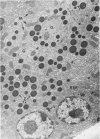

The pathogenesis of a spontaneously occurring exocrine pancreatic insufficiency (EPI) syndrome in CBA/J mice was studied at the ultrastructural level. Initial cytologic manifestations of this syndrome are seen as a progressive digestion of the zymogen granules, beginning at the periphery and proceeding toward the granule interior. Granule membrane breakdown, fusion of neighboring granules, and a release of zymogen contents into the cytoplasm are frequently observed in later stages; in some cases the entire granule contents appear digested before membrane breakdown is observed. In either case, pathologic changes are subsequently observed in mitochondria and rough endoplasmic reticulum. Remnants of lysed cells are then engulfed by invading macrophages, and infiltration by fat cells is observed. Secretory ducts and islets of Langerhans show no pathologic changes even after total autolysis of the exocrine pancreas. Morphologic evidence showing zymogen granule destabilization, coupled with biochemical evidence presented in an accompanying paper, indicate that intracellular autodigestion is the mechanism of exocrine cell death.